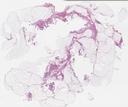

病理切片

Soft-09